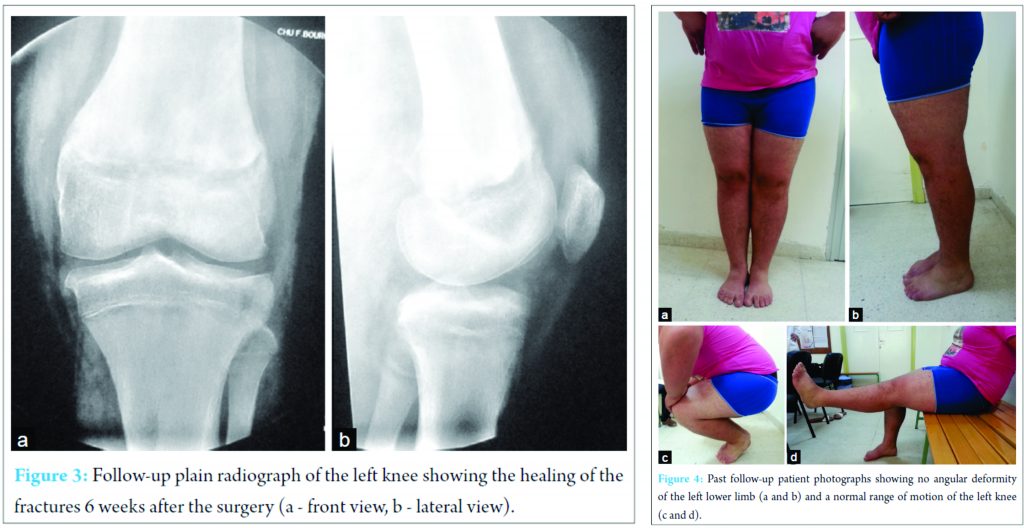

At that time, in front of the spectacular femoral injury, the diagnosis of a Type 3 slightly displaced physeal fracture of the proximal tibia was missed. The patient was operated in the same day. Under general anesthesia, the patient was placed in supine position with the left lower limb pulled in its axis using a fracture table. After a gentle continuous traction, a downward pressure was applied on the distal epiphysis of the femur with the tight been locked. The reduction was found good when checked using the fluoroscopy. Fixation was done using two crossing 24 mm K-wires. A long leg cast was made. Post-operative radiographs showed a good reduction of the distal femur (Fig. 2). At this time, the tibial injury was diagnosed. The slight displacement of the epiphyseal fragment of distal tibia was accepted. Close physical observation in the first post-operative 24 h found no secondary vascular thrombosis. The cast was kept for 6 weeks. After the same period, healing of the fracture was obtained (Fig. 3), hardware was removed, and full weight bearing was allowed. 2 years later, the patient was pain free, with a complete range of motion of the left knee. No angular deformity or shortening of the left lower limb were noted (Fig. 4).